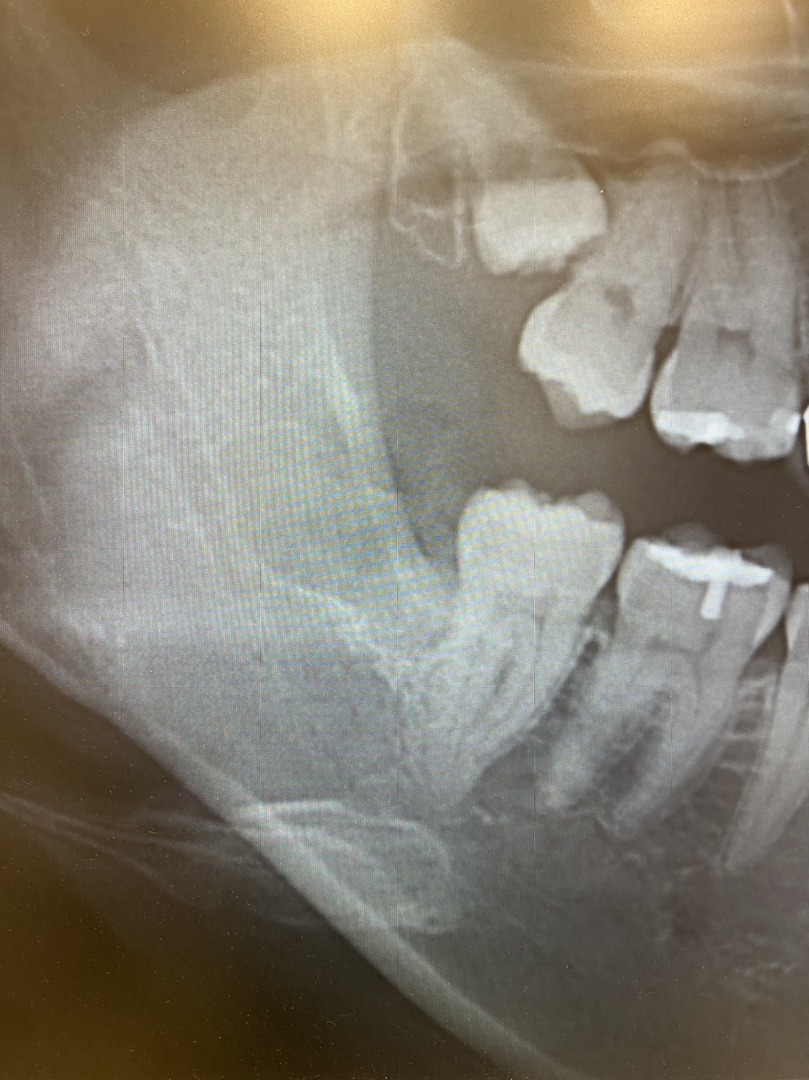

宮園歯科医院では、下顎の親知らずの抜歯(半埋伏抜歯、完全埋伏歯を含む)も行っております。

一般の歯科医院では大学病院に紹介となるようなケースも受け入れております。

半埋伏抜歯、完全埋伏歯は院長がしっかり時間をとって行います。

所要時間は30分程度となります。